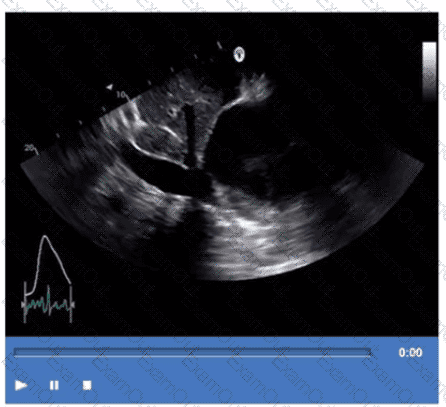

Which vessel is indicated by the arrow on this video?